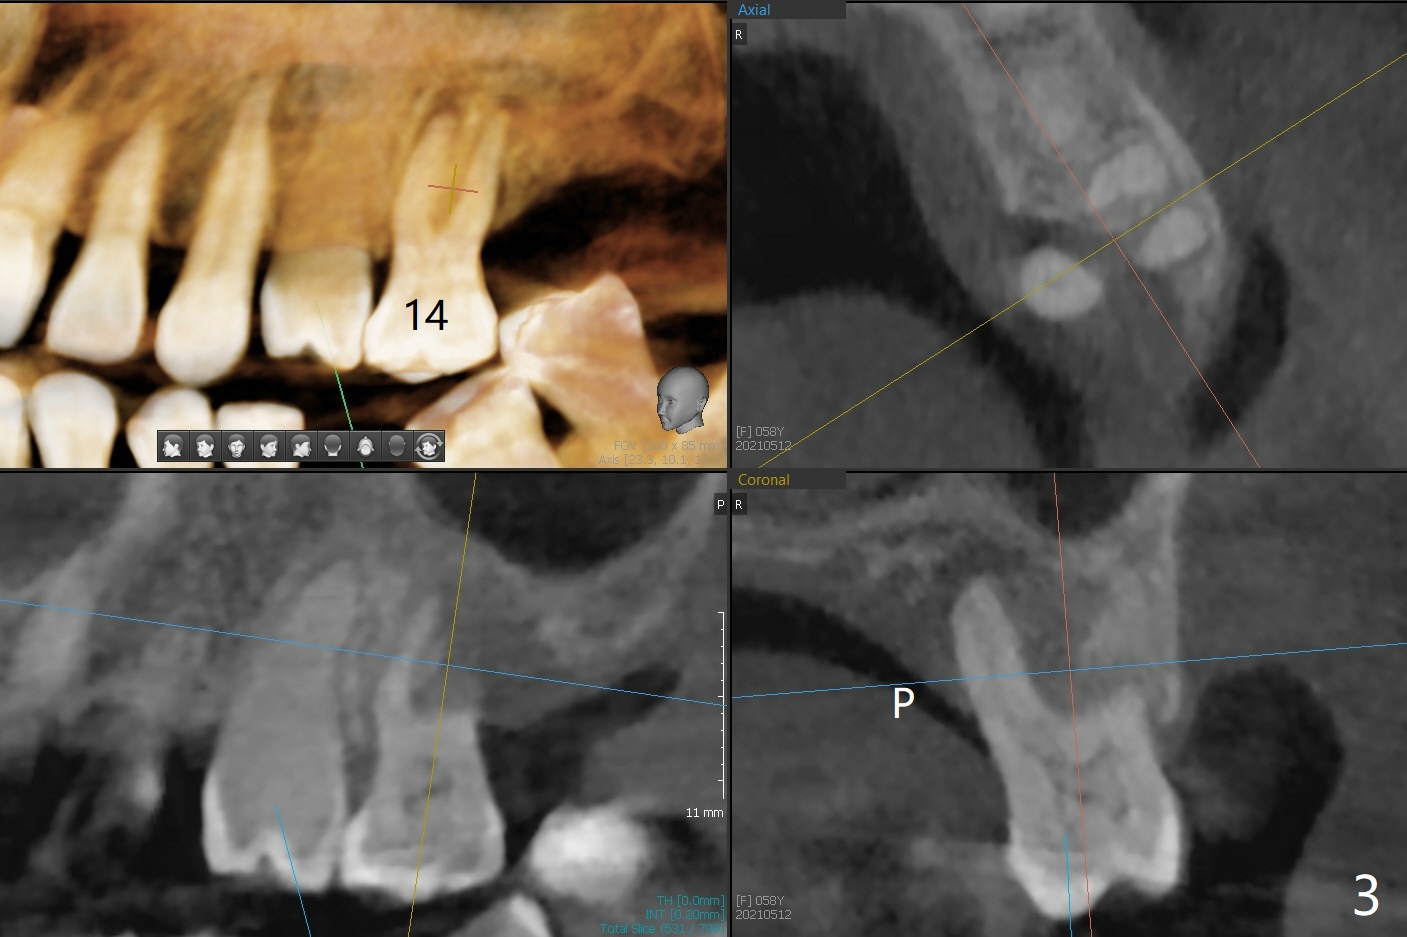

A 58-year-old woman with several restoration agrees to have implants at #15 and 19 (Fig.1). Since #18 tilts mesially, which needs to be trimmed, place #19 implant slightly distal, ~ .5 mm (Fig.2). As the infection at #14 is extensive (Fig.3), place #15 implant (probably 5x7.3 mm) distal, while tilts the long axis of the implant mesially (Fig.4 arrow). Also move the implant palatal with larger diameter and shortened length. Forget about the implant #15 if it is difficult or impossible to change.